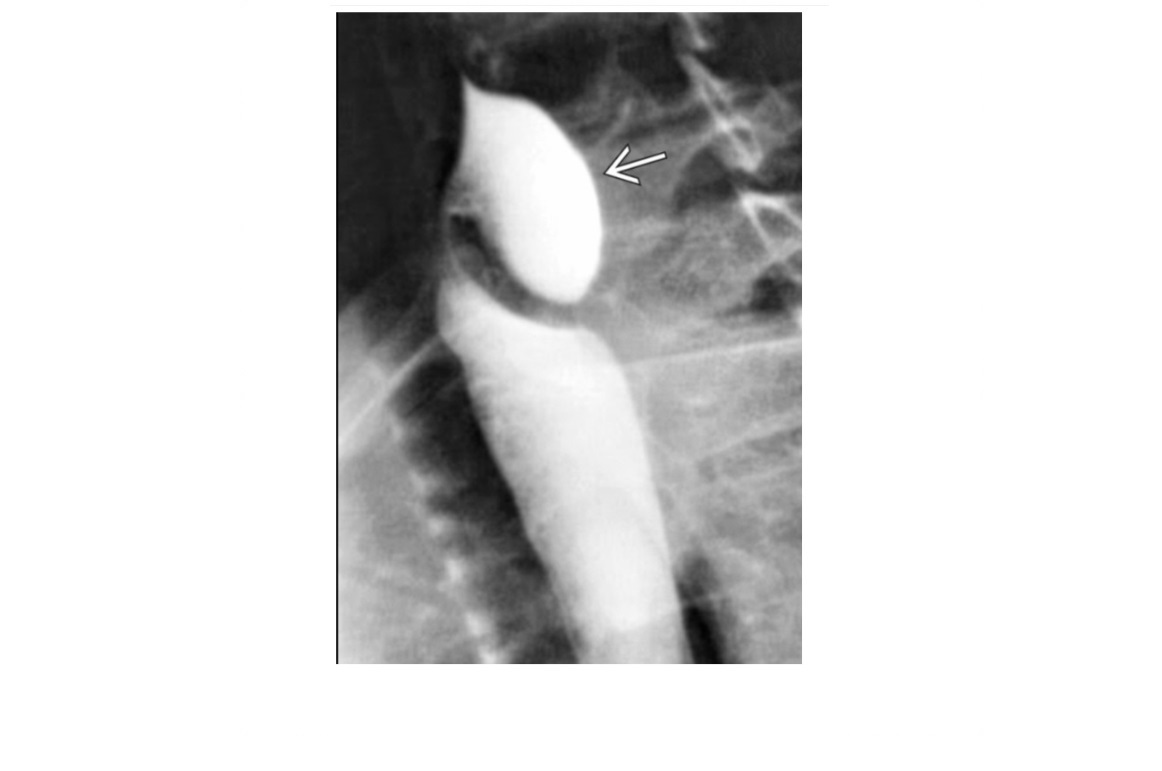

Zenker Diverticulum

Outpouching with rounded contour posteriorly in the neck is above the cricopharyngeus muscle

In hypopharynx!!!

Site of weakness is the Killian dehiscence - between the inferior pharyngeal constrictor muscle and cricopharyngeal muscle